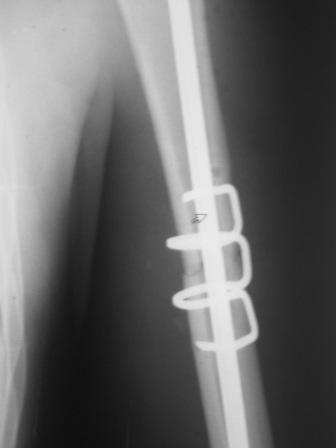

Да, как раз блокированная пластина и стоит, не синтезовская метадиафизарная, Рыбинская, но на порядок дешевле, а профилактика всех осложнений - в данном конкретном случае, начало ранней на вторые сутки - после удаления дренажа разработки движений в смежных суставах. Если же идти с ревизией т.е. всё равно, открыто как вариант небольших разрезов при поперечном переломе можно и комбинированный мос (см.на вкладыше), хотя думаю для такого способа перелом всётаки низковат.

Всё правильно, просто я несколько разрозненно пытался сказать на частных примерах, то , что Вы систематизировали. Совершенно верно данный перелом можно и так и эдак, наиболее оптимально антеградное штифтование, хотя я бы предпочёл пластину LCP(просто - ну лучше у меня это получается и всё, а больному не вредит тот же функциональный способ). А низковато для неблокированного штифтования с конструкциями с термомеханической памятью, то, что представленно на втором снимке.